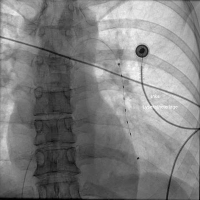

Lysekatheter

Abbildung 2: Platzierung des EKOS-Lysekatheters in die Pulmonalarterie im linken Unterlappen.